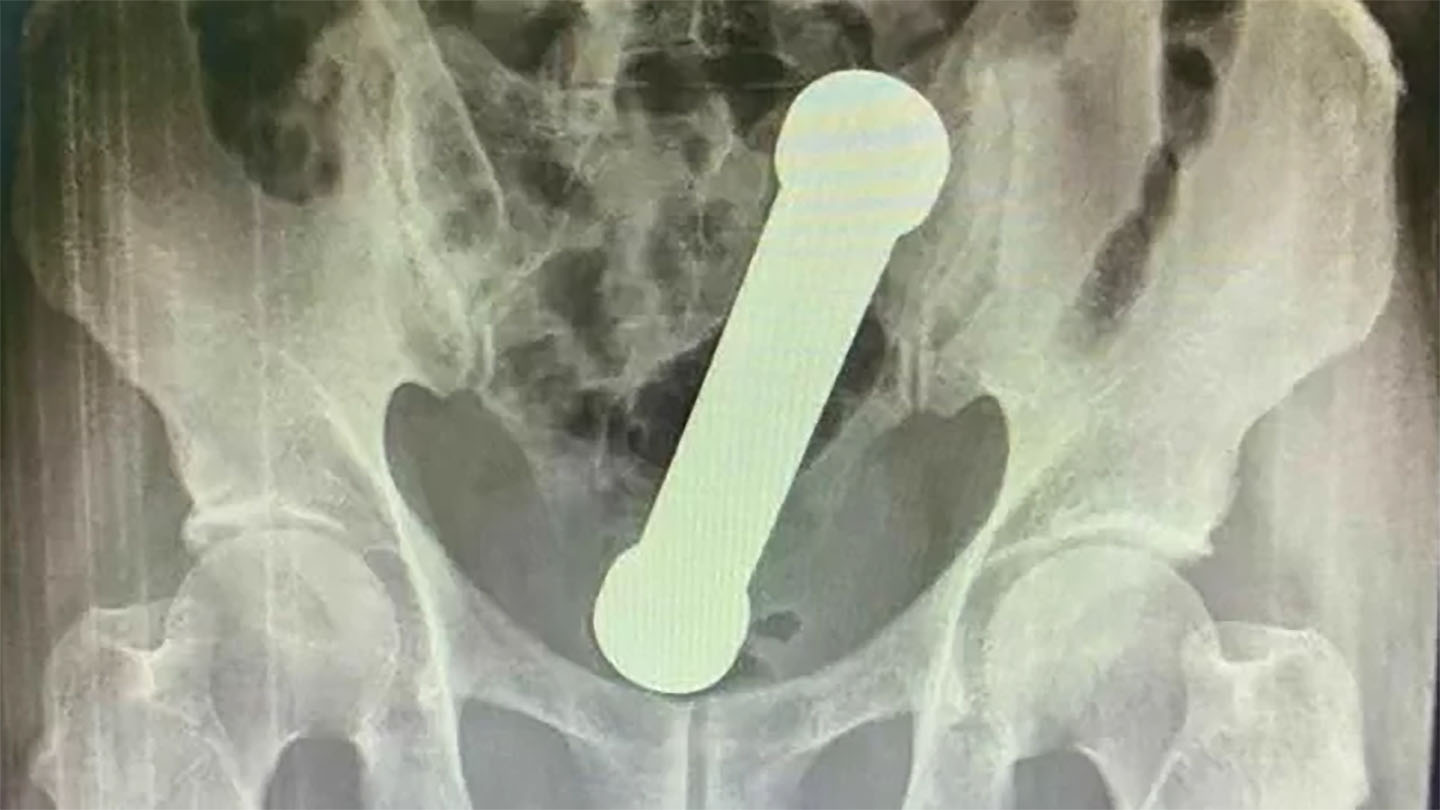

Nas imagens do raio-x foi possível ver um peso de 20 centímetros de comprimento entre o reto e o intestino grosso do paciente.

Os médidos solicitaram o exame e ficaram espantados com a imagem do objeto no resultado. Um haltere de academia de 20 centímetros de comprimento estava localizado entre o reto e o intestino grosso do paciente.